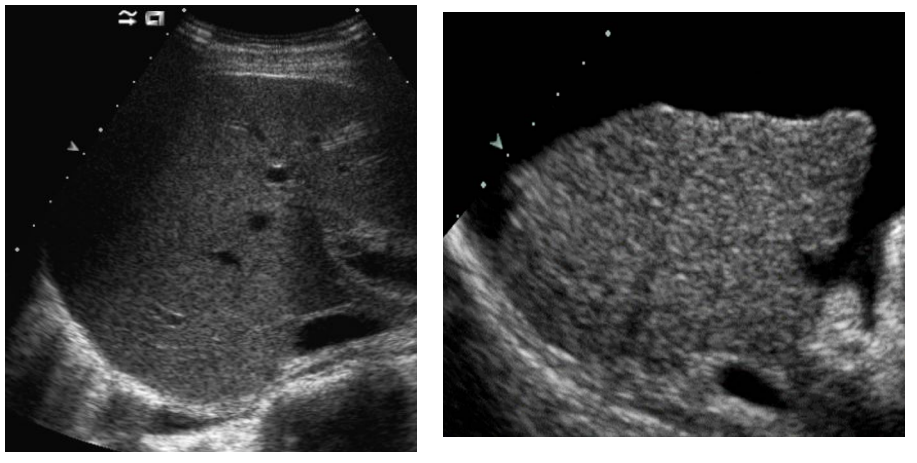

Foie : lésions focales